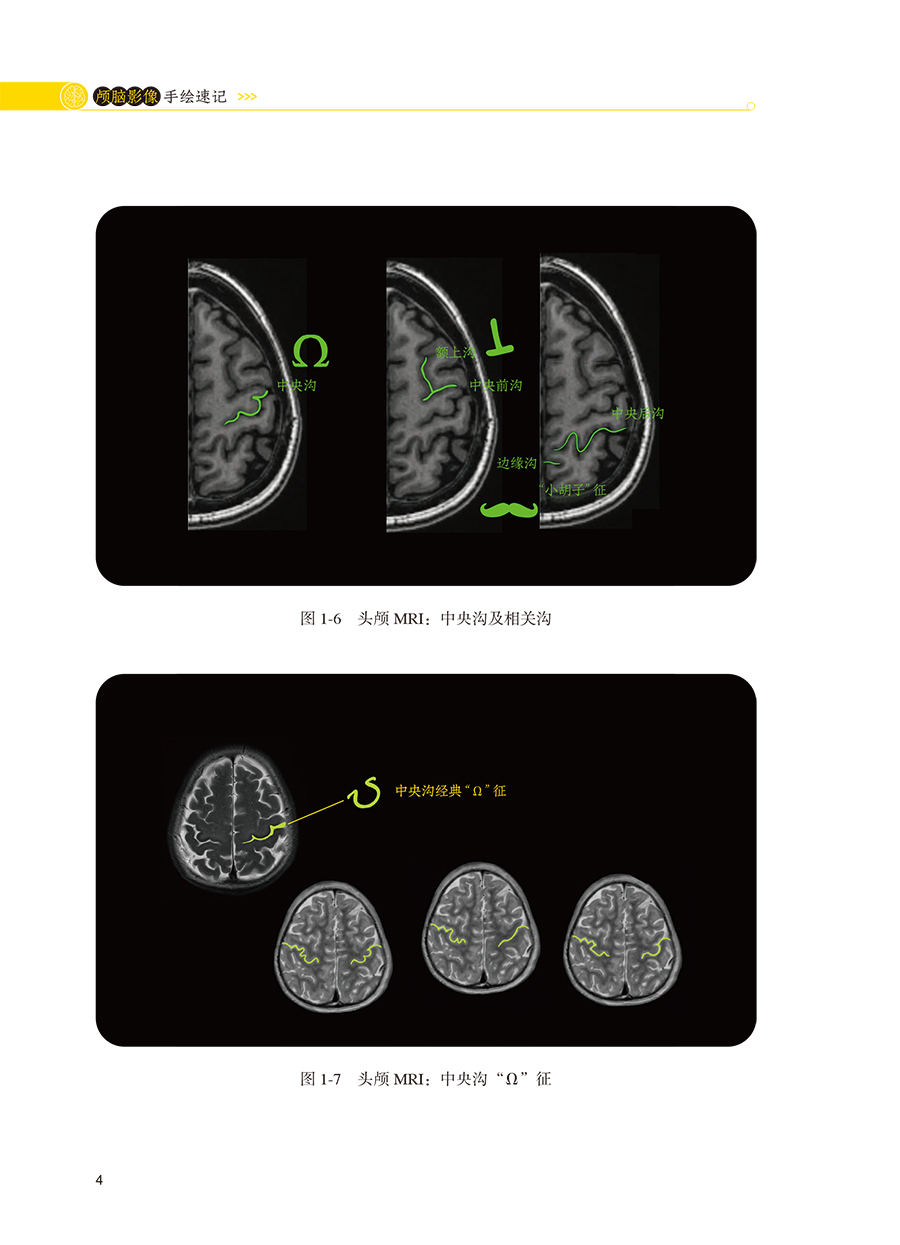

本书内容主要是精练的要点总结性文字和影像图联想记忆手绘的结合,分为正常颅脑影像篇和颅脑病变影像篇两大部分。正常颅脑影像部分主要包括正常生理状态下的颅脑CT和MRI成像特点介绍,及手绘记忆要点;颅脑病变影像手绘主要包括脑血管性疾病、颅内肿瘤、颅脑损伤、颅内感染性疾病、颅脑先天畸形、遗传性脑病、脱髓鞘疾病、癫痫、脑积水等各大疾病分类的CT和MRI影像学特征性表现、疾病发展不同时期的影像学变化特点总结,及手绘记忆要点。本书读者对象主要包括神经、急诊、重症医学、影像等科室医生及相关专业医学生。